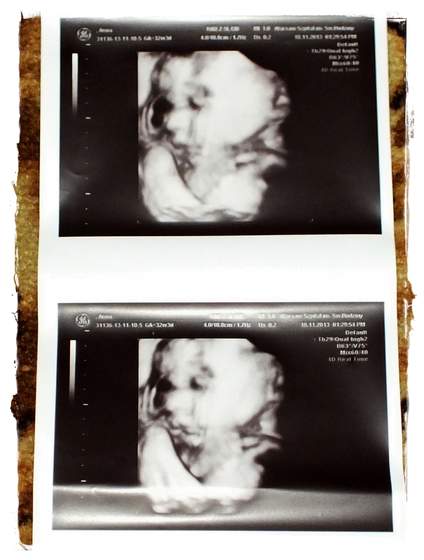

Dziewczyny wszystkie brzuchatki super

)) Ja sobie dziś uświadomiłam, że mój brzuch jest OGROMNY!! Nie wiem ile w pasie, ale łatwiej mnie przeskoczyć niż obejść tym bardziej, że ja z tych niskopiennych 156cm